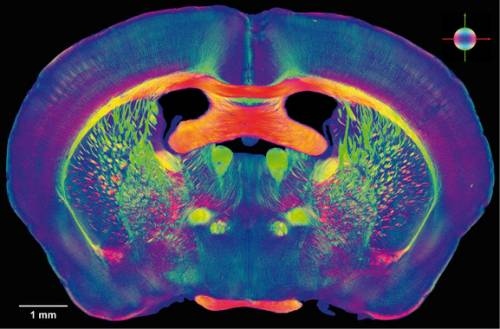

La magnetoencefalografía permite estudiar la conectividad funcional entre distintas áreas cerebrales. (Foto: UPM)

Para ello se registró la actividad magnética cerebral de cada uno de los participantes mediante magnetoencefalografía (MEG), una técnica que permite a los expertos estudiar la conectividad funcional entre distintas áreas cerebrales, o lo que es lo mismo, medir como se comunican entre sí las regiones del cerebro en cada uno de los participantes.